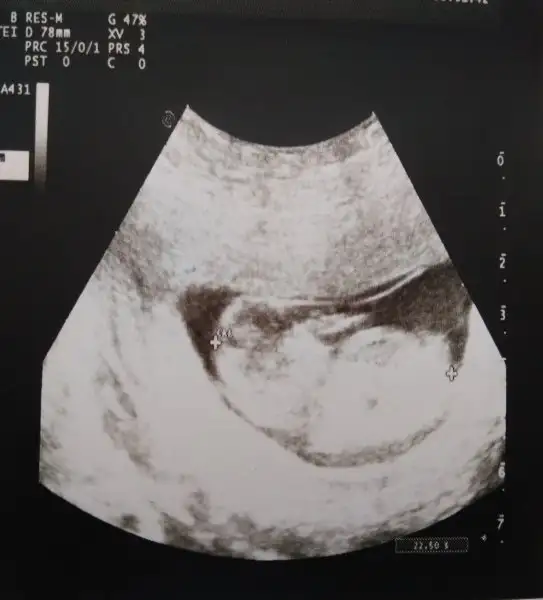

ERkek olbilirBenim bebeğim teyzelerine küsmüş kimse onun şeysini göremedi diyeEki Görüntüle 2086277